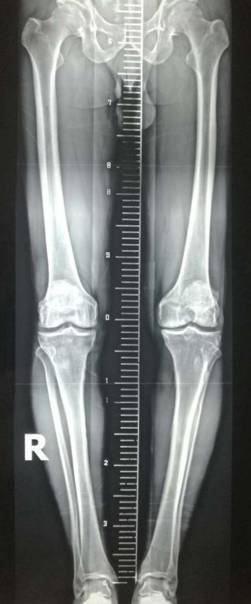

术前术后对比

全膝关节翻修术

全髋关节翻修术